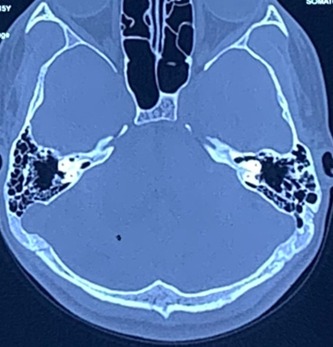

chronic-ear-2

• CT scan (if cholesteatoma suspected)

chronic-ear-3

The surgical plan is customized after detailed ear examination, hearing tests, and CT imaging when required.